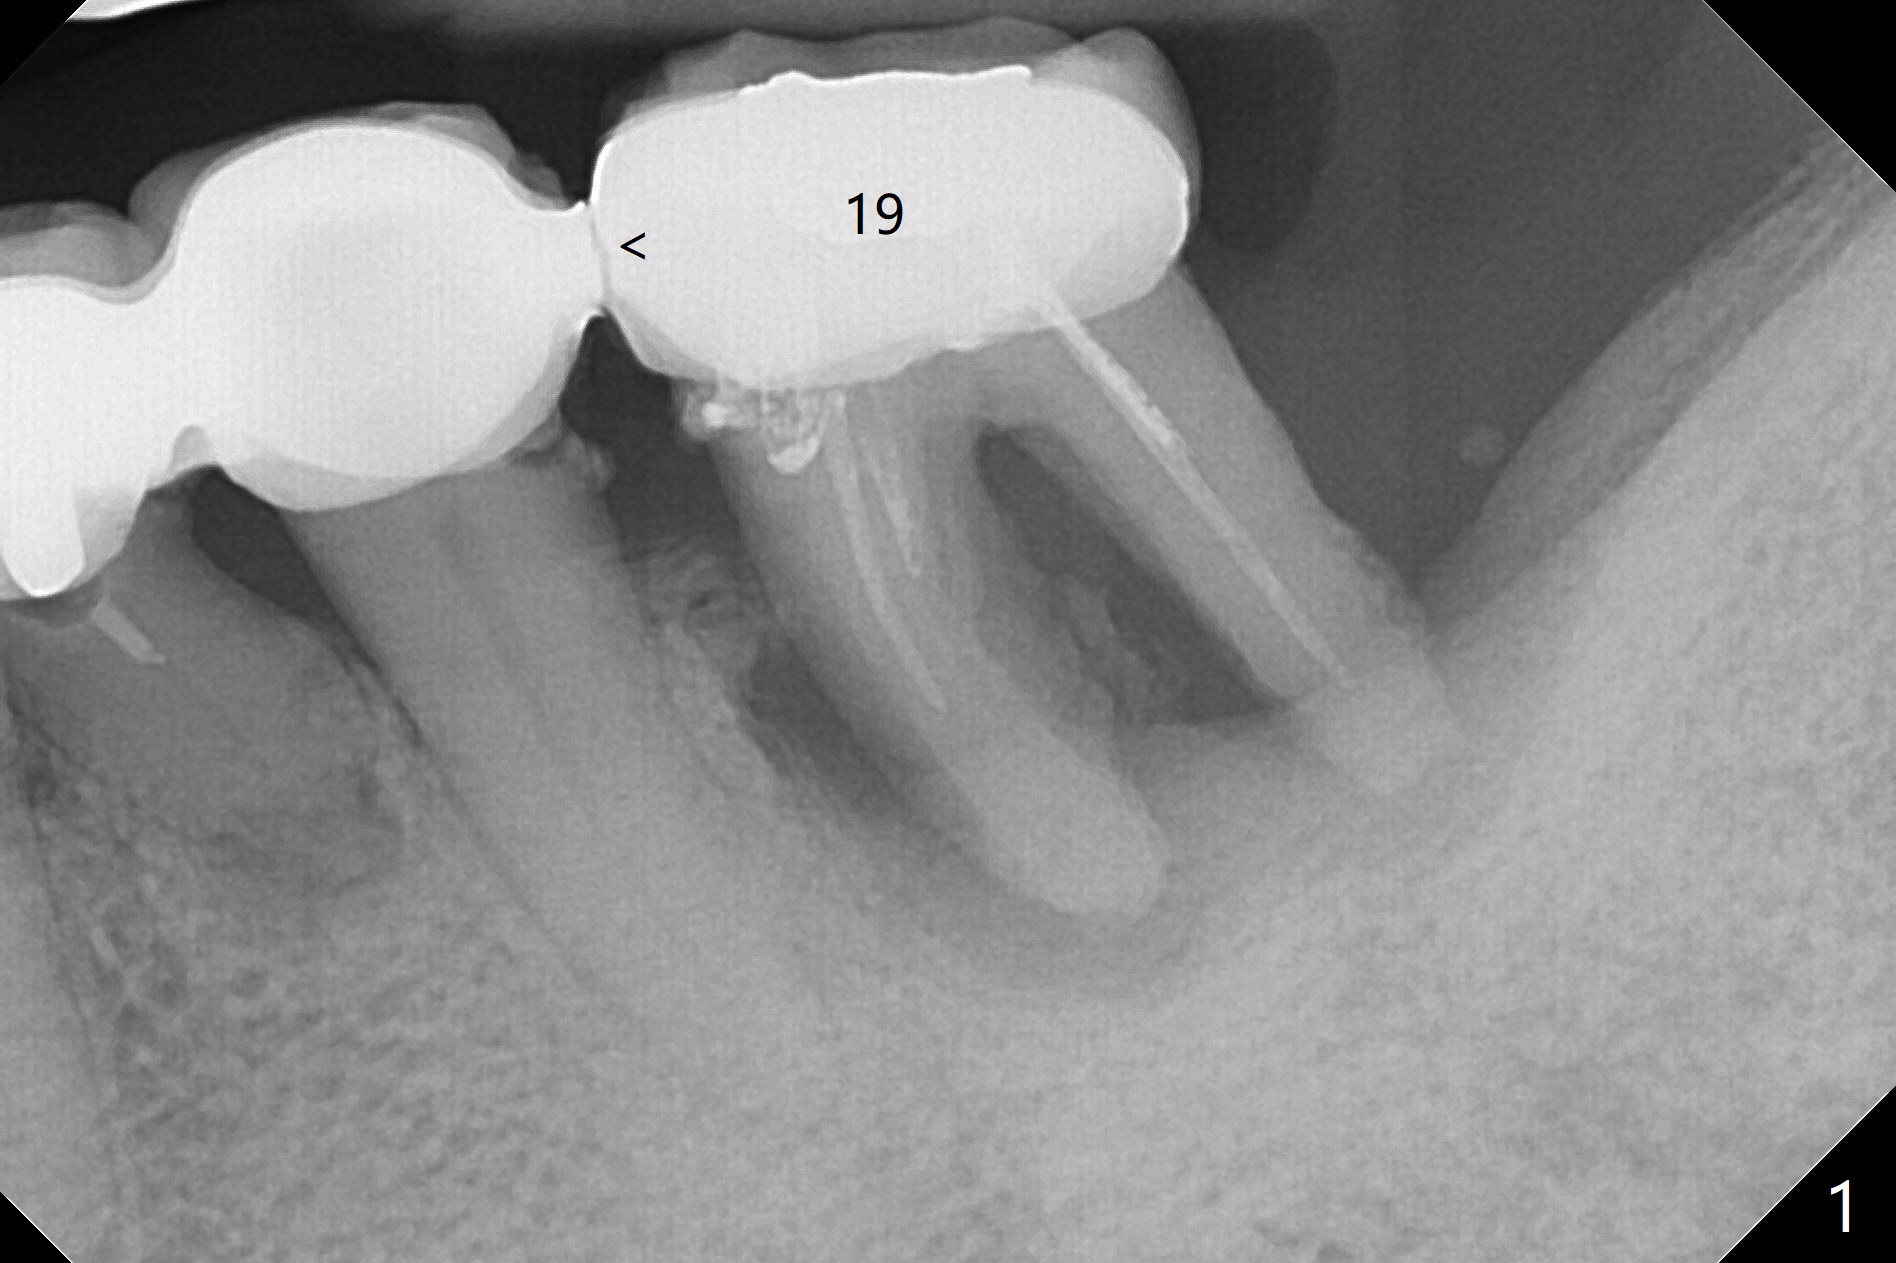

A 73-year-old woman cannot masticate on the left. It appears that the retainer at #19 breaks from a long-spanned FPD (Fig.1). After extraction and gross debridement, Vanilla graft is placed in spite of severe bone loss (Fig.2 *). She has returned once for follow up. The soft tissue heals. She has left the country.